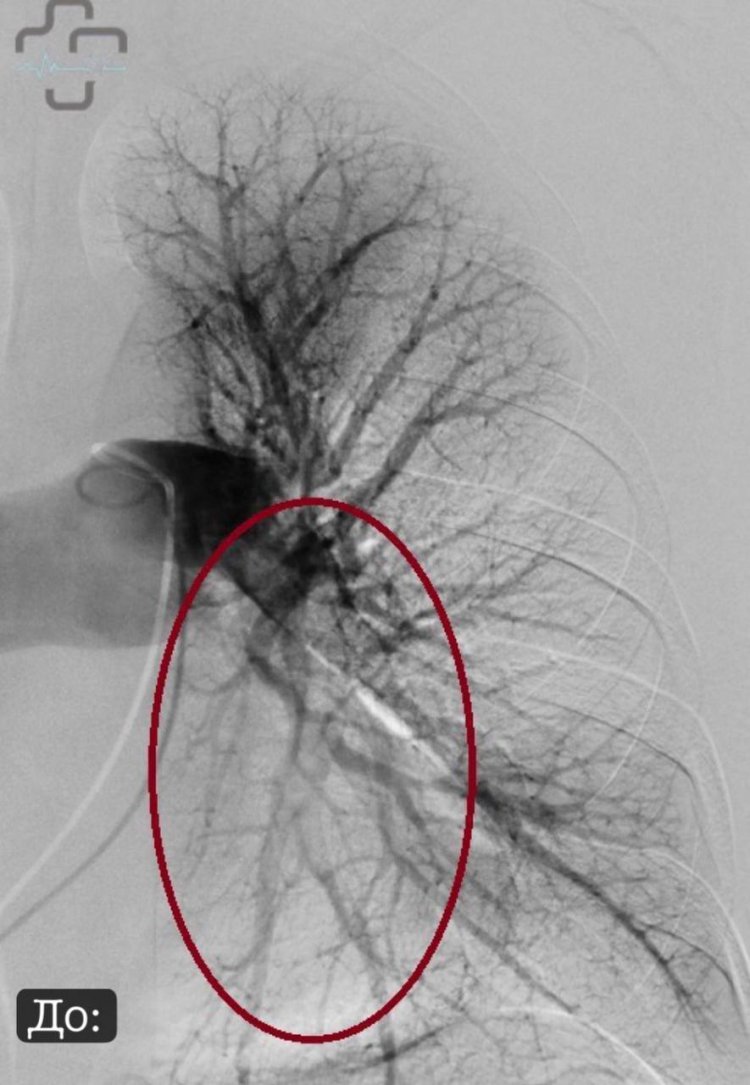

Ультразвуковой транскатетерный локальный тромболизис легочной артерии в горбольнице Орска, Фото: горбольница Орска

В Оренбургской области впервые успешно провели уникальную и очень сложную операцию — ультразвуковой транскатетерный локальный тромболизис легочной артерии. И провели ее врачи городской больницы Орска. Отметим, что в России данные вмешательства впервые выполнены в 2024 году

Пациентка из Оренбурга поступила в областной центр с диагнозом тромбоэмболии легочной артерии — опасной и жизнеугрожающей ситуации. Обычно для лечения используют антикоагулянты или системный тромболизис, когда в вену вводят лекарство, разжижающее тромб. Но этот метод имеет свои риски в виде возможных кровотечений. Тогда было принято решение перевести женщину в Орск для проведения сложного вмешательства.

Пригласили пациентку в рентген-операционную, выполнили ангиопульмонографию (контрастное исследование легочной артерии), подтвердили массивность тромбоза легочной артерии, и уже окончательно показания к операции определили. Доступом через бедренную вену, это малоинвазивная процедура, сделали небольшой прокол на бедре, через катетеры, которые мы доводим до зоны тромба в левой легочной артерии, устанавливается в данную зону катетер специальный с ультразвуковым датчиком внутри него, и в шахты вводится лекарство.

После введения минимальной дозы тромболитика был достигнут точечный эффект именно в нужной зоне. Это значит — меньше побочных эффектов, меньше опасений и больший шанс на успешное выздоровление.

Тромбоэмболия: до и после, Фото: горбольница г.Орска